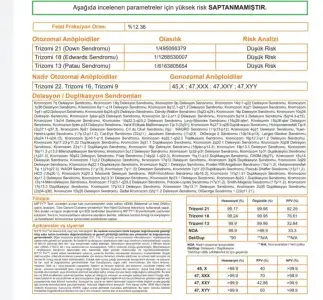

Nifty test sonucum cikti sukur ki temiz geldi aglamaktan icim disima cikti sevincten. Cinsiyeti artik merak ediyorum ama raporda yok. Doktorum benimle de paylasmadilar soylerlerse paylasirim dedi. Gercekten de ayni e-mail ile gondermisler. 20. Haftayi beklemez heralde. Bir de taradiklari seylerden anlasiliyo fln yazmislar internette ama rapora bakinc bana pek bisi ifade etmedi. Bilen varsa gondereyim

Benim raporumda yazıyordu herşey. Paylaşın isterseniz bakalım.Nifty test sonucum cikti sukur ki temiz geldi aglamaktan icim disima cikti sevincten. Cinsiyeti artik merak ediyorum ama raporda yok. Doktorum benimle de paylasmadilar soylerlerse paylasirim dedi. Gercekten de ayni e-mail ile gondermisler. 20. Haftayi beklemez heralde. Bir de taradiklari seylerden anlasiliyo fln yazmislar internette ama rapora bakinc bana pek bisi ifade etmedi. Bilen varsa gondereyim

Siz nerde yaptirmistiniz, benim GenoksBenim raporumda yazıyordu herşey. Paylaşın isterseniz bakalım.

Benimki panorama idi. Raporun ortasında bebeğin kromozom yapısı yazıyordu. Sizinkinde yazmıyor.Siz nerde yaptirmistiniz, benim Genoks